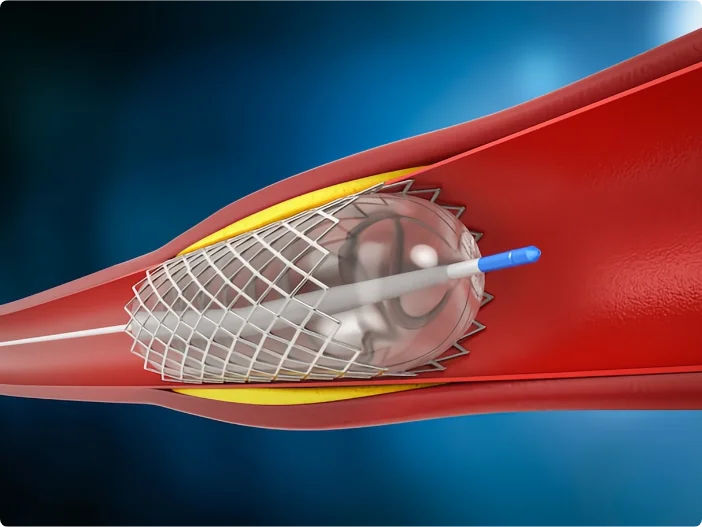

โรงพยาบาลมะเร็งสมัยใหม่กว่างใช้วิธีการรักษามะเร็งแบบใหม่ “การแพทย์ผสมผสานระหว่างจีนกับตะวันตก และการผ่าตัดแบบบาดแผลเล็ก” โดยใช้ทคนิค เช่น การรักษาแบบคีโมเฉพาะจุด การฝังรังสี การใช้มีดคังโป การจี้ด้วยคลื่นไมโครเวฟ มีดนาโน และการรักษาด้วยความเย็น ซึ่งจะมีการวางแผนการรักษาเฉพาะบุคคลตามสภาพร่างกายและความต้องการของผู้ป่วยด้วยเทคนิคการรักษาแบบบาดแผลเล็ก

- 01 ไม่ต้องผ่าตัดใหญ่ ลดภาวะแทรกซ้อน: รักษาหน้าอกได้ดีที่สุด โดยใช้อุปกรณ์ผ่านแผลเล็กๆ เพื่อลดการติดเชื้อและภาวะแทรกซ้อนหลังผ่าตัด

- 03 แผลเล็ก ผลข้างเคียงน้อย ฟื้นตัวเร็ว: เป็นการผ่าตัดแบบไม่เปิดแผลขนาดใหญ่ ช่วยลดความเจ็บปวดและช่วยให้ฟื้นตัวเร็วขึ้น ทำให้มีคุณภาพชีวิตของผู้ป่วยดีขึ้น

เทคนิคหลักของการรักษาแผลเล็ก